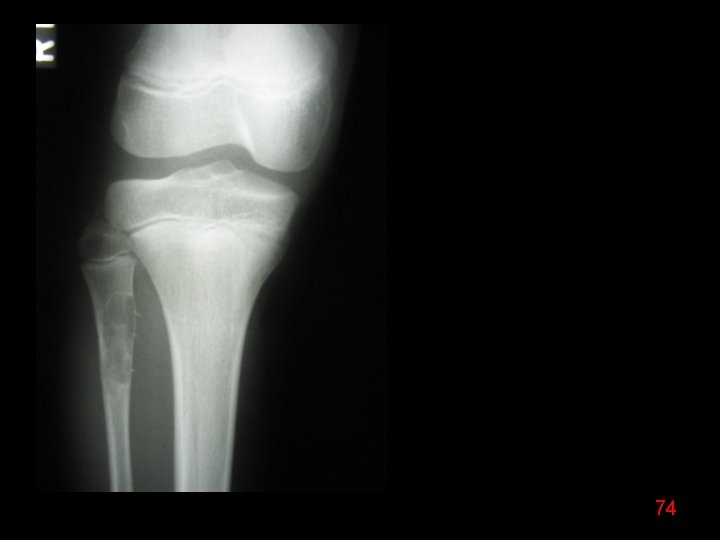

74